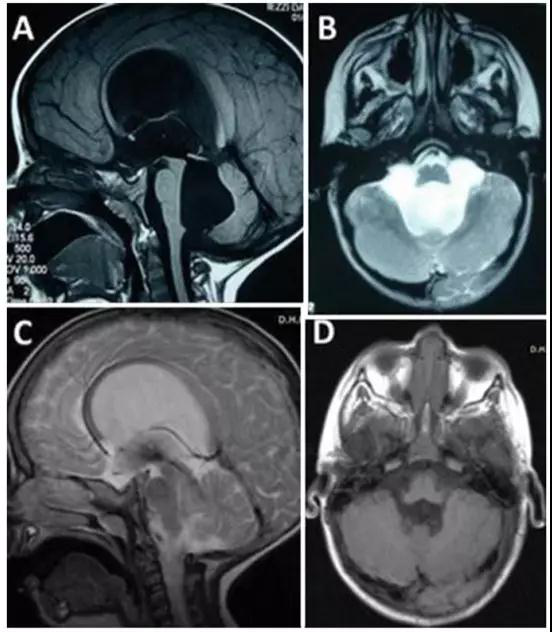

INC国际神经外科医生集团旗下组织国际神经外科顾问团(WANG)成员Concezio Di Rocco教授作为国际神经外科联合会基金小儿脑积水项目负责人,在脑积水手术方面经验丰富。在一份报告中,教授为一名因四脑室出口狭窄导致脑积水,合并小脑功能异常共济失调的3岁大的小男孩进行内镜下三脑室造瘘术,成功控制了脑积水的产生,手术过后小男孩症状迅速消退,预后效果好。

由于四脑室出口狭窄引起的脑积水小脑功能障碍,患有脑积水的3岁男孩。A、B为其术前影像,C、D显示内镜下三脑室造口术成功控制脑积水,术前症状迅速消退。